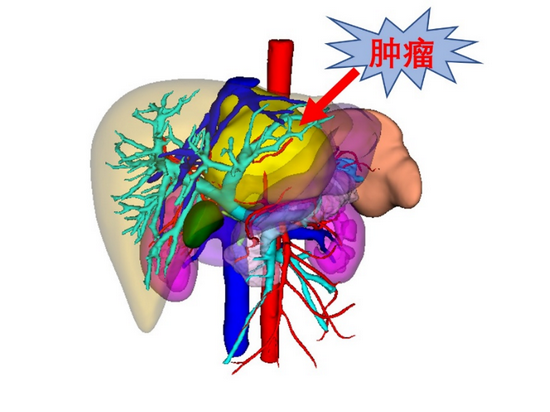

【曙光·新闻】我院肝胆外科采用3d可视化技术完成肝肿瘤精准切除

图片尺寸633x647